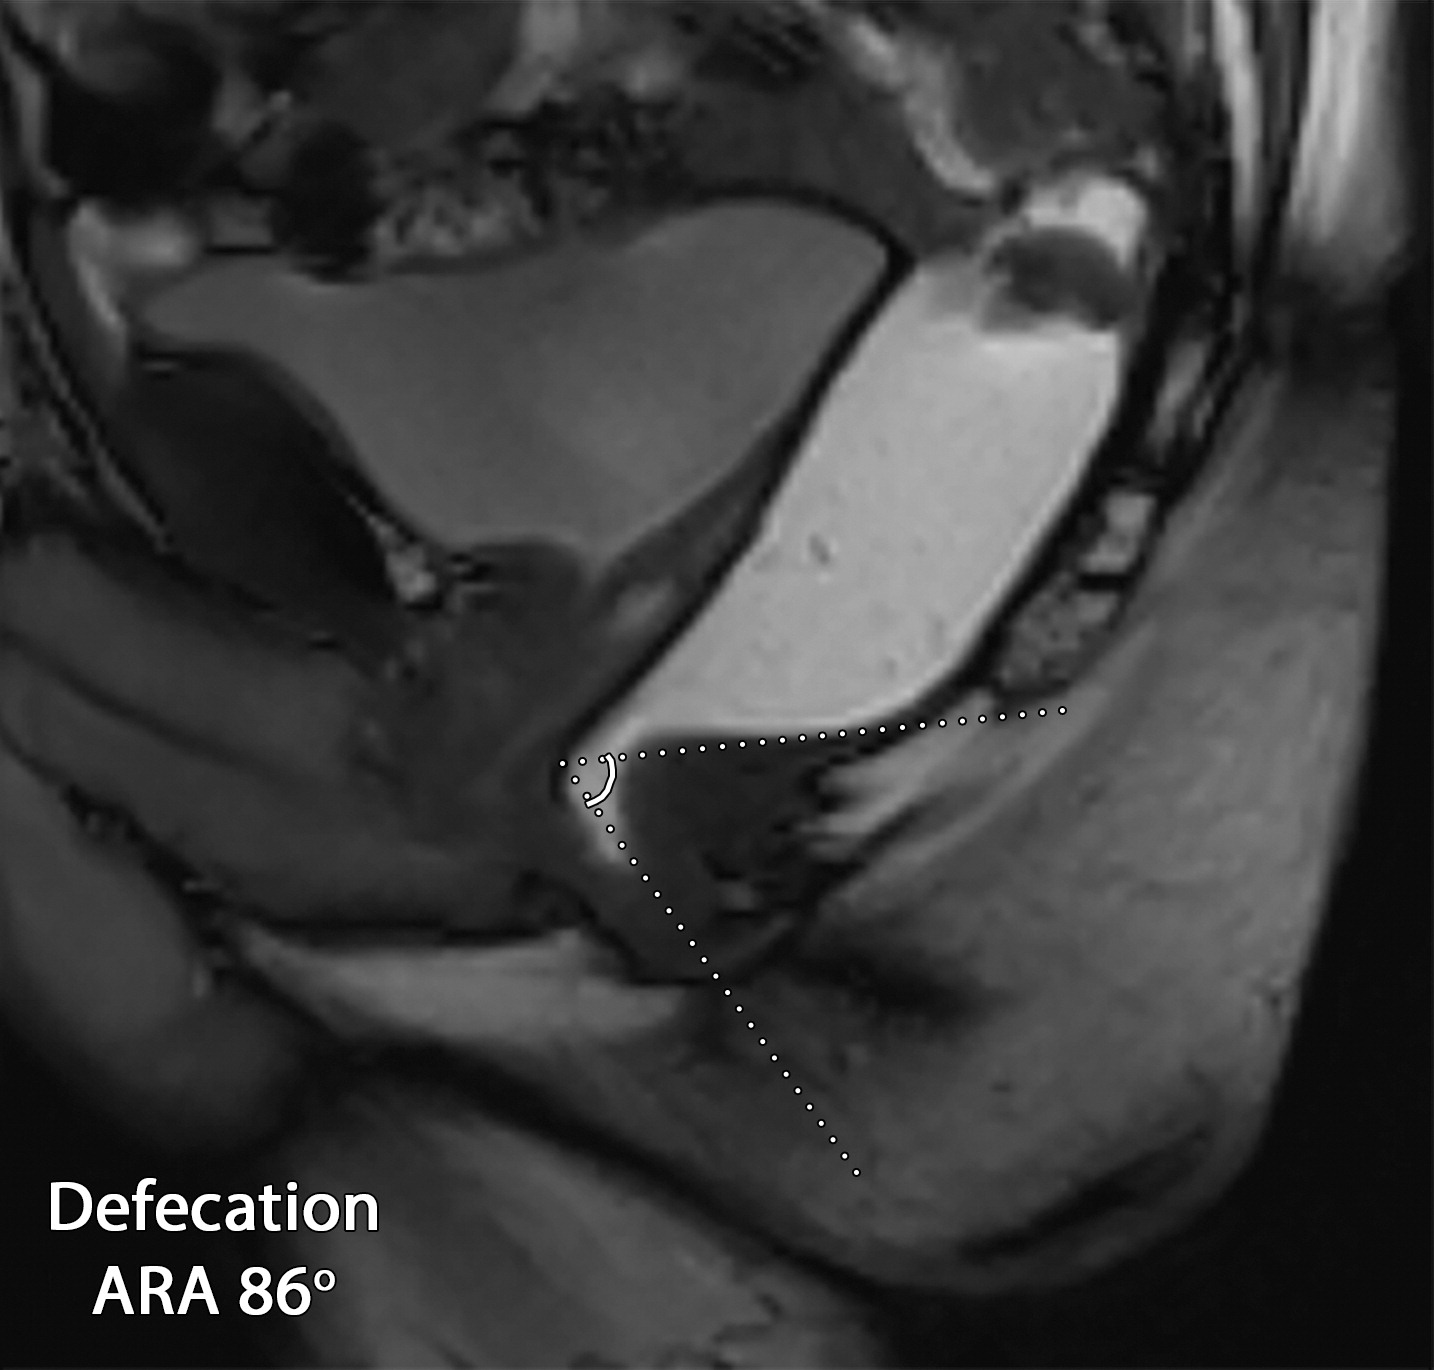

a54a1cb8cfeaf259eec8f4d8f79de20f.jpeg5bd0d167d41482a652f0e12d75b5e4a4.jpeg9414a04737a9077a8760c398f38476f8.jpeg

肛门直肠角(ARA);

28岁协同动作障碍患者,a图静息态ARA为104°,b图在排便时ARA为86°,这是由于耻骨直肠肌的反常收缩。c图示双侧耻骨直肠肌增厚(c图白色长箭头)。